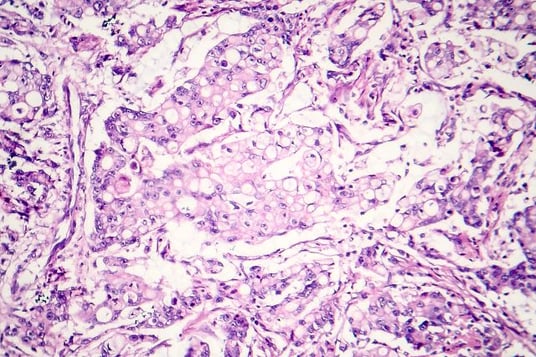

Immunohistochemistry (IHC) is a cornerstone technique in both research and diagnostic laboratories, playing a vital role in identifying biomarkers within tissue samples. For researchers seeking to validate IHC assays, navigating the regulatory landscape is often complex. This article discusses critical aspects of assay development, regulatory pathways, and practical steps for successful clinical trials and assay commercialization.

Validation ensures that an IHC assay is reliable and reproducible for biomarker detection in clinical settings. The purpose of an assay directly correlates with the level of validation required. Assays designed for research purposes require less robust validation than those meant for informing patient care treatment decisions. The intended use, sample collection region, and patient risk determine the regulatory strategy, which in turn informs the laboratory strategy for IHC assay development and validation.